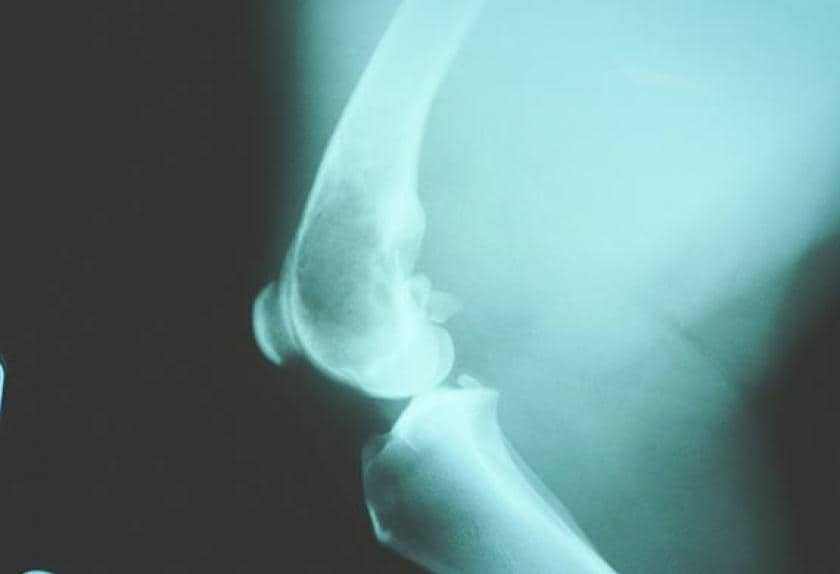

My 9.5 year old male, golden retriever, had a limp 4 ...

My 9.5 year old male, golden retriever, had a limp 4 ... from ww2.justanswer.com